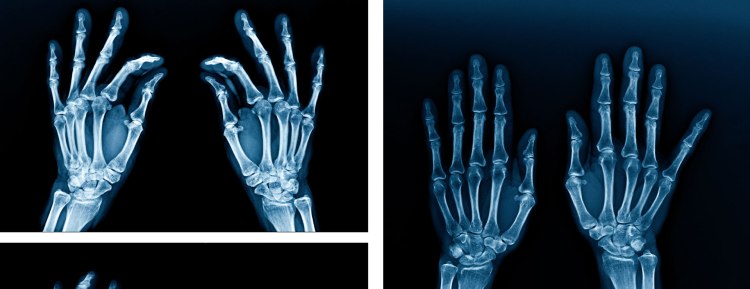

Los rayos X usan haces de energía que pasan a través de los tejidos del cuerpo hacia una película especial y forman una imagen. Muestran imágenes de sus tejidos internos, huesos y órganos. El hueso y el metal se ven blancos en las radiografías.